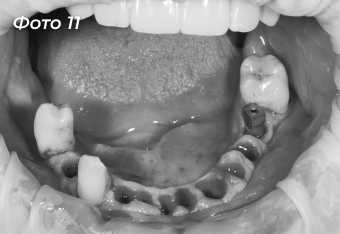

Через 4 месяца после первой операции было проведено оперативное вмешательство на нижней челюсти. Была выбрана другая тактика, были удалены сразу все зубы (Фото 11).  Установлено 6 имплантов  (Фото 12) по хирургическому шаблону  (Фото 13).